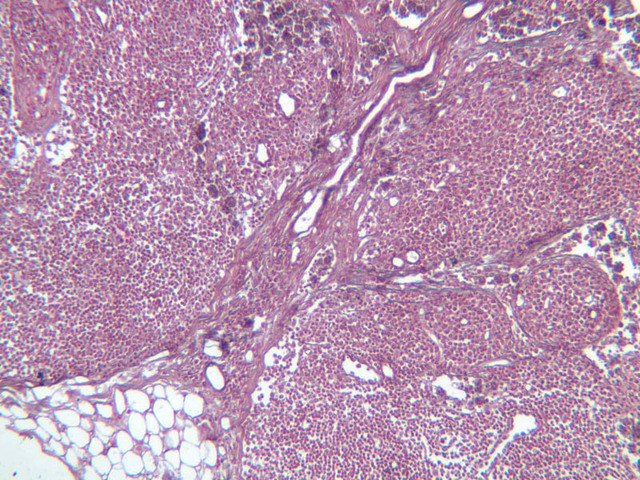

Sections through the spleen (slides A-36, aniline blue [2.5x, 10x, 20x-labeled, 40x] [2.5x, 10x-labeled, 20x-labeled, 40x]; A-37, retic [2.5x, 10x, 20x-labeled, 40x]; A- 37, H&E [2.5x-labeled, 10x, 20x, 40x]; A-38, H&E [10x, 20x, 40x]; A-39, H&E [2.5x, 10x, 20x, 40x]) show a thick investing capsule composed of collagenous tissue and smooth muscle, typically covered with mesothelium. In slide A-36 muscle and collagen are brightly stained. The capsule and mesothelium completely surround the organ and the fibrous portion enters the splenic substance at the hilus around the splenic arteries and veins forming trabeculae of fibromuscular tissue within the splenic substance. This fibromuscular tissue enables the spleen to expel blood by contracting. Identify trabeculae as fibrous partitions in the section and look for blood vessels within them.

Where the trabecular arteries pass into the splenic pulp, they become invested by a sleeve of lymphoid tissue. This lymphatic tissue collectively forms the white pulp of the spleen (A-36 [2.5x, 10x, 20x, 40x]). It also is referred to as the periarterial lymphatic sheath or PALS. On an H&E stained section (A-38 [2.5x, 10x, 20x, 40x] [2.5x, 10x, 20x, 40x]) the white pulp will appear as basophilic clumps of lymphoid cells. The arteries of the white pulp are called central arteries, although they may be displaced to one side of the lymphoid sleeve by the presence of a nodule. The majority of cells forming the PALS are T lymphocytes. In places the covering of lymphatic tissue is enlarged due to the presence of lymphoid nodules (splenic or Malphighian corpuscles) which are comprised predominantly of B lymphocytes.

The remainder of the cellular mass in the spleen is red pulp (A-38 [10x, 20x, 40x]), made up of red and white cells of the blood enmeshed in the reticular tissue of splenic cords and present in the splenic sinuses. After passing through the PALS, the trabecular arteries branch to form smaller arterial vessels known as penicillar arterioles which narrow, forming arterial capillaries that empty into the cords of the red pulp (open circulation) or into the venous sinuses (closed circulation). In the splenic sinuses the cells of the blood are exposed to red pulp macrophages. The splenic sinuses eventually become confluent to form veins that enter the trabeculae and gradually merge meeting in the hilus to form splenic veins.

Examine the composition of the red pulp tissue. The three dimensional structure of the red pulp is analogous to Swiss cheese with the holes being the venous sinuses and the cheese being the parenchyma (i.e. splenic cords). On slide A-36 which is stained with Mallory's aniline blue locate examples of the splenic sinuses ([2.5x, 10x, 20x, 40x-labeled] [10x, 20x, 40x]). The walls of the splenic sinuses consist of adjoining specialized endothelial cells whose nuclei in many cases stand out from the wall in a bead-like fashion. The basement membrane of the epithelial cells stains blue revealing the sinuses quite nicely. Usually the sinus lumen is filled with red cells and leukocytes. The skeletal framework of the cords is provided by a network of reticular fibers. As above, the reticular cells are best seen using a reticular fiber stain (slide A-37 [2.5x, 10x, 20x, 40x-labeled]). Look for the large pale nuclei of reticular cells that have darkly stained reticular fibers. Fibers run irregularly in the cords, but clearly outline the sinuses around which they are wrapped. Notice on this same slide that there is much less reticular tissue in the white pulp than the red. The splenic cords occur around the sinuses and are distinguished by the presence of disintegrating red blood cells undergoing phagocytosis.